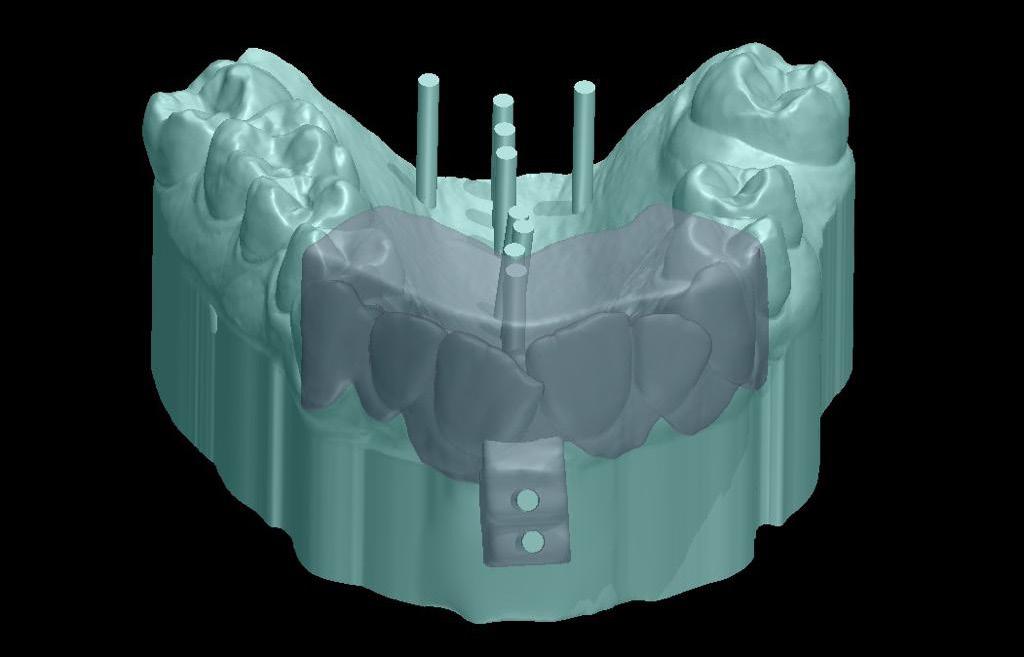

IJO Fall 2024 by internationaljournaloforthodontics - Issuu